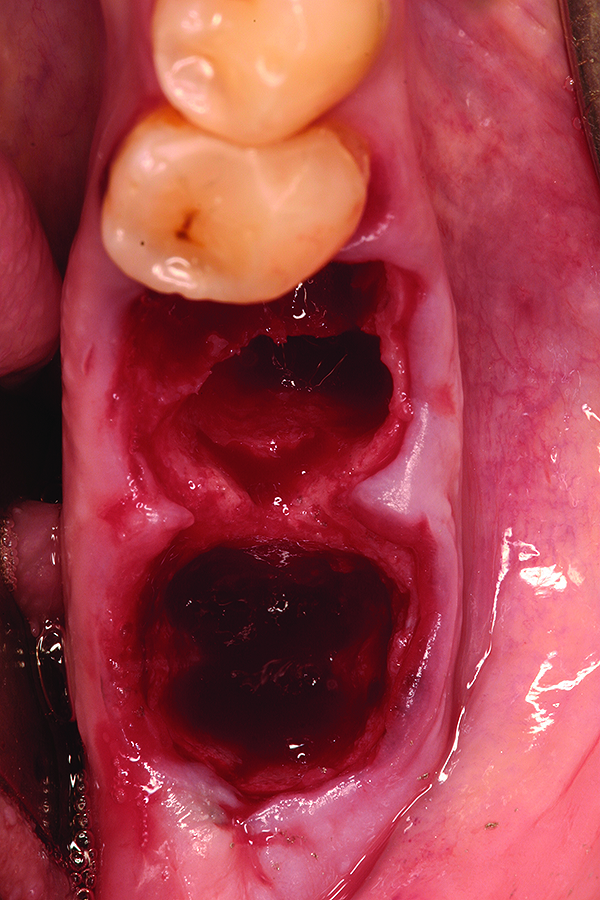

Fig 9. Note the significant osseous defect in the buccal osseous wall following atraumatic tooth extraction.

Figure 9